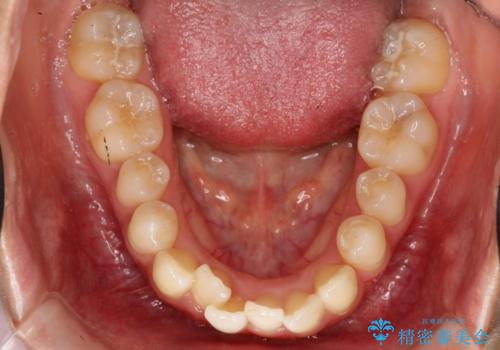

初診時の歯並びの状態としては、上下ともに全体に及ぶの中等度以上のがたつき(叢生)があり、前歯数本が反対交合の状態でした。

強い叢生がありましたが、抜歯は行わず上下顎ともに、主に歯列弓の拡大とディスキング(歯と歯の間に隙間を作る処置)を行い叢生を改善しました。